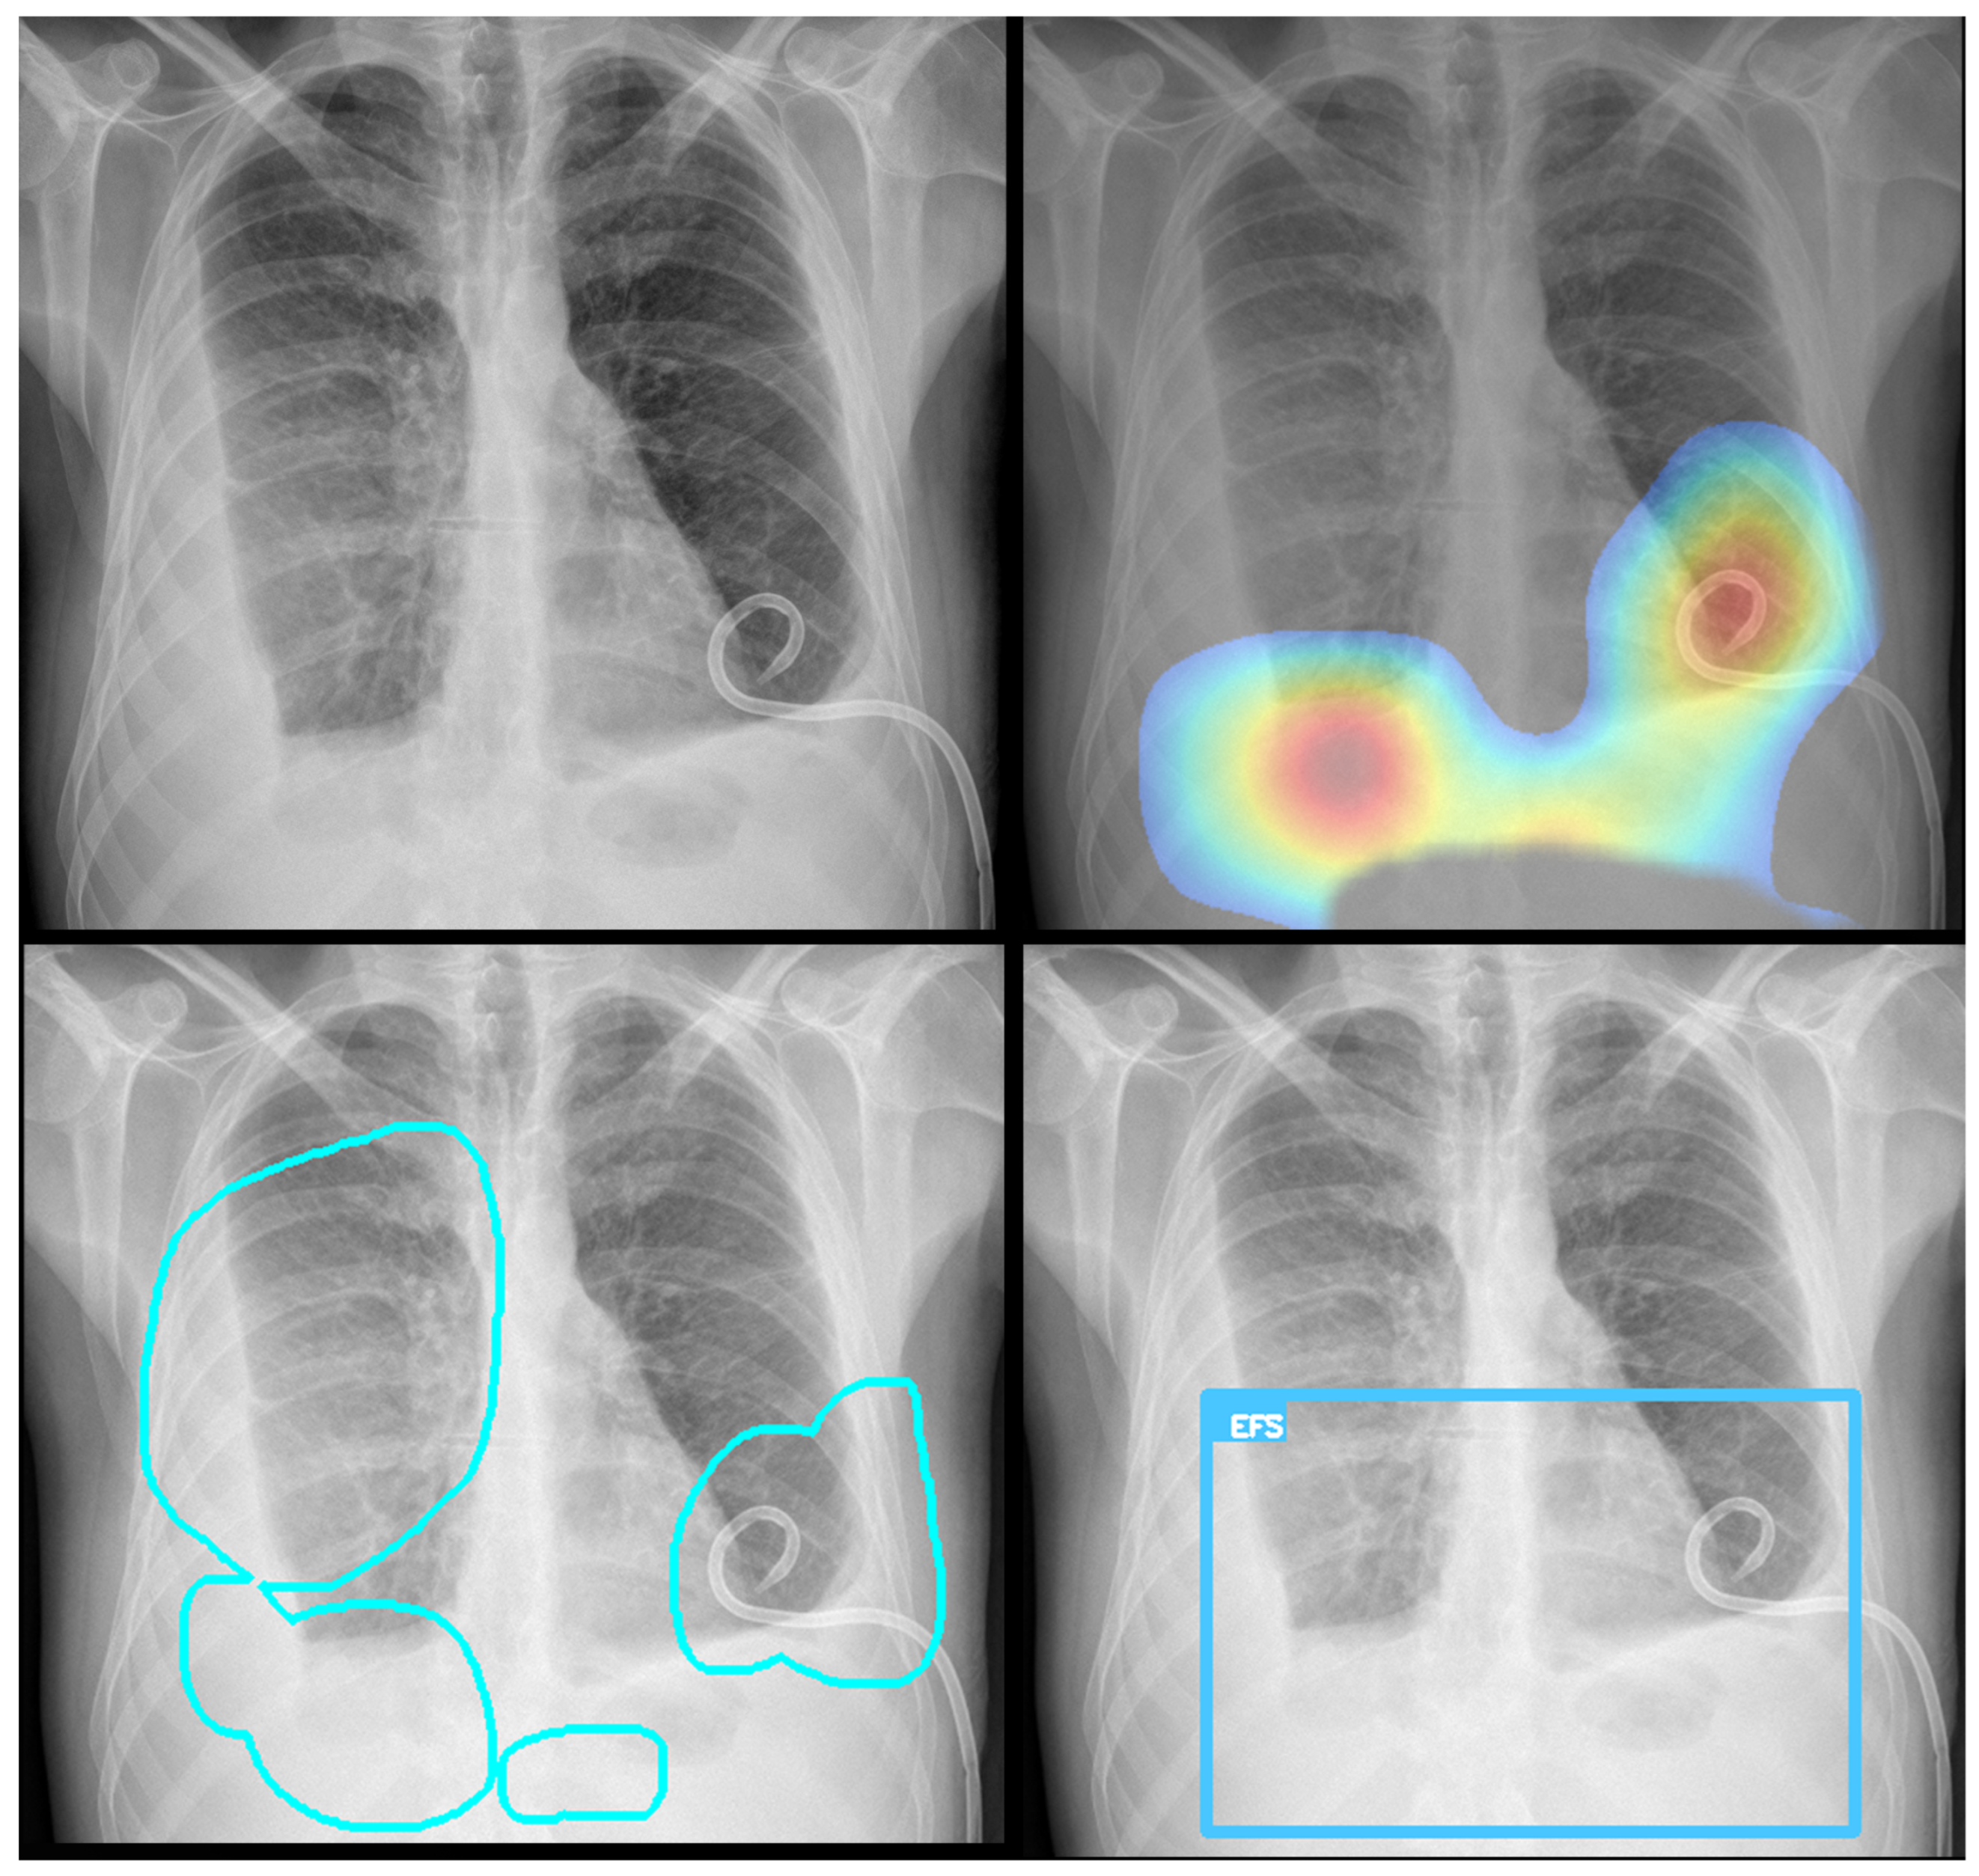

To enhance model transparency and validate spatial reasoning, we applied Gradient-weighted Class Activation Mapping (Grad-CAM) to visualize the regions most influential in classification decisions. Grad-CAM served a dual purpose in this context: first, it verified that the model’s predictions are based on clinically relevant regions within the segmented thoracic area; second, it contributed to interpretability by generating intuitive heatmaps that highlight the anatomical structures driving the model’s output. This step was crucial for improving classification accuracy and verifying that it relied on the correct visual cues, aligning with radiological expectations. For optimization, they were only generated when the classification probability score was above the defined threshold.

Representative Grad-CAM overlays are shown in Figure 3, Figure 4, Figure 5 and Figure 6, illustrating several different types of pathologies. These visualizations demonstrate where the algorithm focuses attention on the appropriate pathological regions, thereby reinforcing the validity and interpretability of the proposed pipeline.

3.3. Error Analysis

An analysis of the algorithm’s false negatives revealed a nuanced performance profile, where a specific miss did not always equate to a complete system failure. Across the board, a substantial number of cases with a false negative for a particular pathology were nevertheless correctly identified as abnormal by the general “yes-finding” classifier or had other co-occurring true positive pathologies. For example, out of 38 false negatives for opacity, the algorithm correctly identified the exam as abnormal in 25 cases. In many instances of a missed finding, the algorithm successfully detected other pathologies within the same study. Misclassification was another notable source of error, where an existing pathology was detected but incorrectly labeled, such as opacities being predicted as masses or nodules (Figure 4). Radiologist review of these false-negative cases frequently noted findings that were “subtle,” “small,” “doubtful,” “seen on lateral image only,” or “non-specific.” In other cases, the algorithm correctly identified a more critical finding, like a large pleural effusion, while missing a secondary, less significant pathology (Figure 3). Figure 9, Figure 10 and Figure 11 illustrate false negative cases for opacity, pneumothorax, and nodule, respectively. This highlights the inherent limitations and inevitable failures of this kind of system.

Figure 3. Example of Grad-CAM visualizations localizing detected findings. The figure shows the original image (top left) alongside three types of explanatory outputs generated by the algorithm: a heatmap (top right), a contour outline (bottom left), and a bounding box (bottom right). All visualizations are derived from the same process, showcasing different output options.